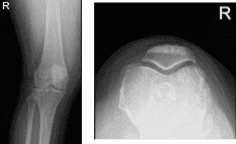

She presented her Xray results, for her left knee there are mild osteoarthritic degenerative changes. For the right knee, there are moderate osteoarthritic degenerative changes. There are no fractures and there are no acute fractures.

No definite surfacing medial or lateral meniscal tear is seen. Moderate sized Baker’s cyst. For the right knee, Complex degenerative tear in the medial meniscus extending from the body into the posterior horn into the posterior root with extrusion. Tricomparmental articular cartilage denudation with marginal bony spurring.

XR of Right Knee Lateral Oblique View